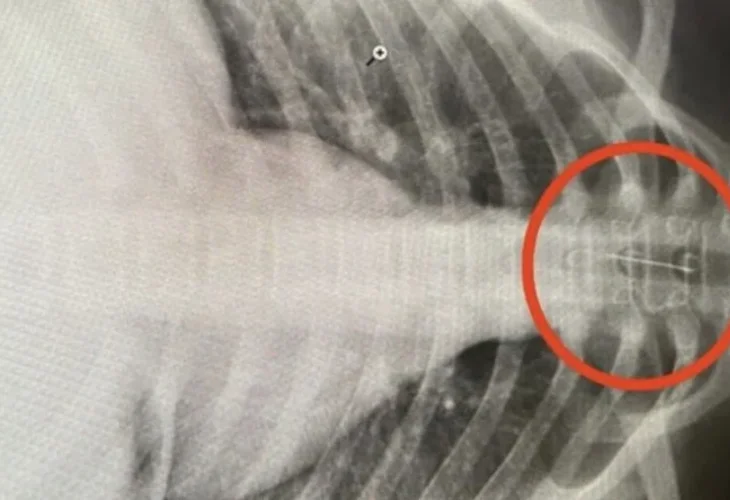

Dr. Ilyshat Riskuzhin recounted the incident. He explained that the girl was suffering from intense chest pain, had difficulty breathing, was coughing, and experienced uncontrollable drooling. An X-ray examination revealed the presence of the needle in her trachea: "We saw a small needle causing havoc in her body. We immediately consulted with specialists and decided to transfer her for urgent surgery at the hospital in Ufa."

The quick actions of the hospital in Ufa, where doctors specialize in a procedure known as bronchoscopy, were critical in saving the girl's life. "The rapid intervention was crucial in this case," the surgeons said. "When a foreign object is 'wandering free' in the body, there's no telling what it can damage, especially something as sharp and thin as a needle."